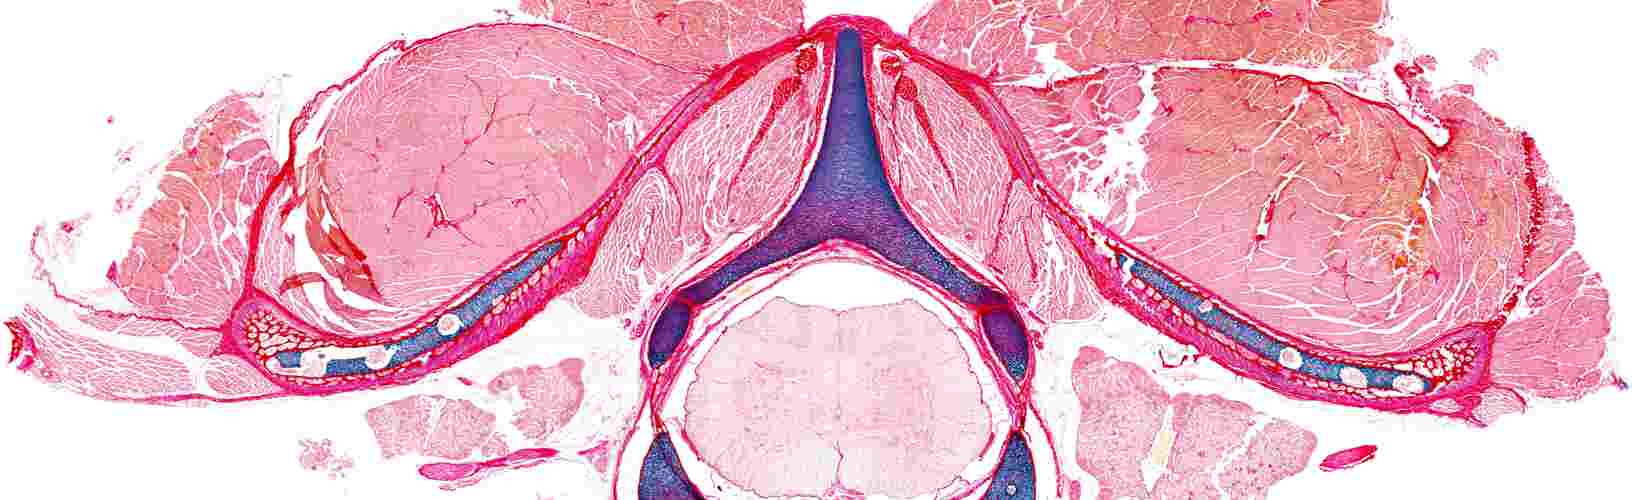

Chick vertebral histology

Transverse histological view of a thoracic vertebra from an embryonic chick, stained to show cartilage (blue) and collagen (red/ pink). Spinal ligaments are stained dark red positioned adjacent to muscle, symmetrically connecting rib cartilage to vertebral processes. This approach provides opportunity to examine the maturation of spinal tissues during development.